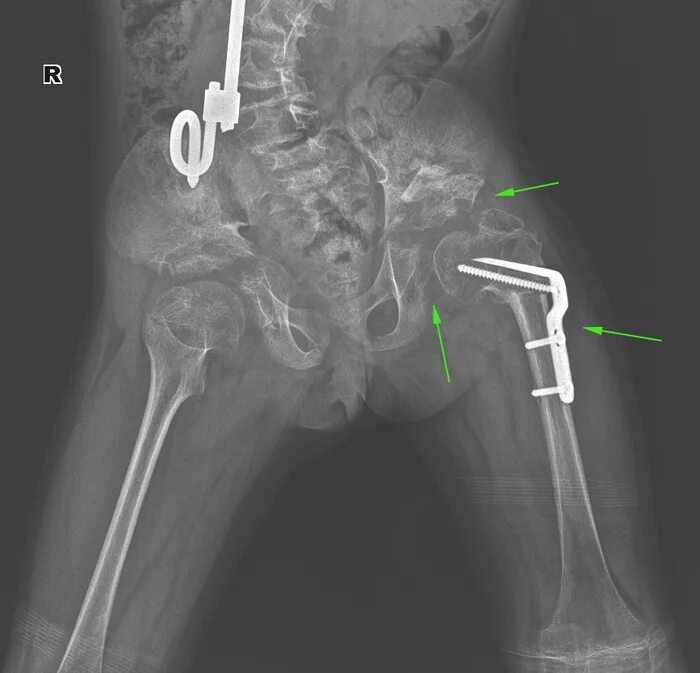

Рентген тазобедренный в двух проекциях